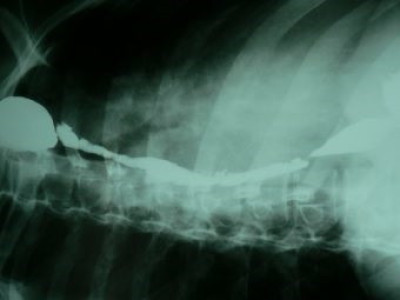

Dilatación esofágica con balón

Envíado por Dr. Carlos Miguel Zavaleta Consuegra